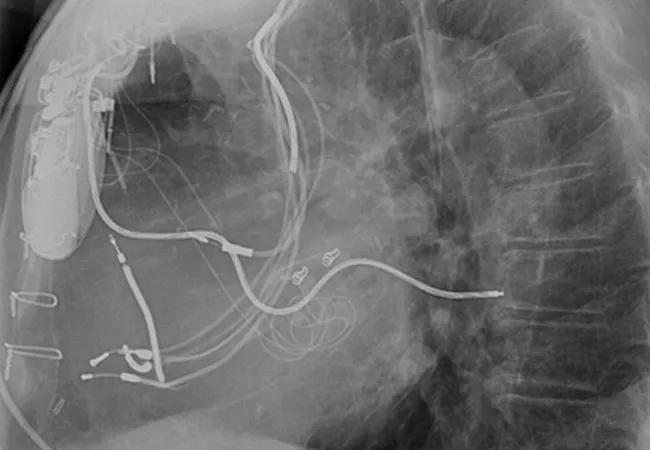

chest X-ray from Dr. Wazni showing abandoned leads.

As the popularity of cardiac implantable electronic devices (CIEDs) explodes, the number of infections linked to abandoned leads is growing exponentially. These unwanted leads complicate the management of CIED infections and result in worse outcomes, including death, Cleveland Clinic electrophysiologists have found.

The 1,386 patients with infected devices were divided into two groups: those with (23.3 percent) and those without (76.7 percent) previously abandoned leads. Failure to achieve the study’s primary end point — successful removal of the device and all lead material from the vascular space without a major complication — was significantly more common in patients with abandoned leads (13.0 percent) than in patients without abandoned leads (3.7 percent) (P < .0001).

“It’s a growing problem for us, because we deal with the ones that get infected,” he says. “After about a year, the leads get attached to the veins or atrium and develop fibrosis. It becomes difficult to release them from their binding sites without causing damage.”